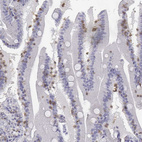

Immunohistochemistry analysis in human lymph node and small intestine tissues using HPA040957 antibody. Corresponding CD3E RNA-seq data are presented for the same tissues.